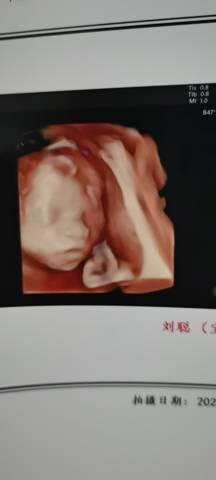

四维彩超,不知道是男孩还是女孩哦

努力的大反 2021-12-09 20:52

你好。我们是判断不了男宝宝跟女宝宝的,孕期定期检查,我觉得宝宝健康就好的。祝心想事成 。

你好亲爱的,通过这个来判断男孩女孩是不太准确的哈。那么这个男孩女孩都是我们最爱的宝贝哈,我们要给他同等的关爱和呵护,也祝你可以如愿以偿,心想事成,祝你好运。